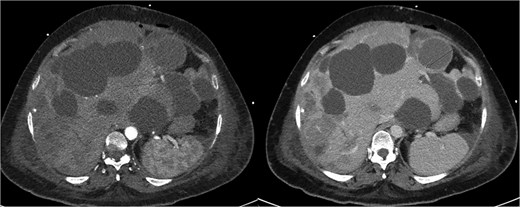

The patient initially improved but deteriorated on post-operative day 4. Repeat CTMA demonstrated active haemorrhage in segment 2—remote from the operative field—and ischaemic changes in segments 6/7, despite a patent portal vein and hepatic artery inflow (Fig. 2). Despite resuscitative measures there were increasing vasopressor requirements, leukocytosis, and deteriorating liver function tests (bilirubin 135 μmol/L, ALP 667 μ/L, GGT 551 μ/L, ALT 234 μ/L, AST 535 μ/L). Differential diagnoses included biliary sepsis, secondary infection of ischaemic liver, ischaemic hepatopathy with progressive liver failure, and angiography complications such as arterial dissection flap. Angiography failed to demonstrate active haemorrhage for an embolization target and CT liver triple-phase showed increased intrabdominal free fluid.

Repeat CTMA with arterial enhancement within the left hepatic lobe (arrow, left image), appearing more ill-defined with contrast pooling on delayed phase (arrow, right image) suggestive of active haemorrhage.